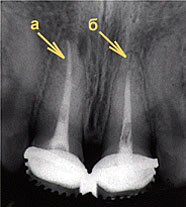

Пломбирование каналов

Пломбирование каналов: а) полное; б) неполное.